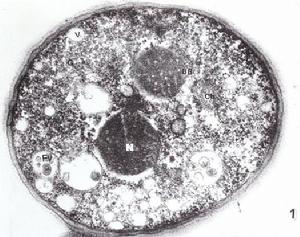

臨床表現

痢疾菌圖(2)普通型:起病急、高燒、大便每天10次以上,內有粘液膿血,便後有沉脹、下墜感。患兒全身乏力、食慾減退、噁心、嘔吐、陣發性腹痛。